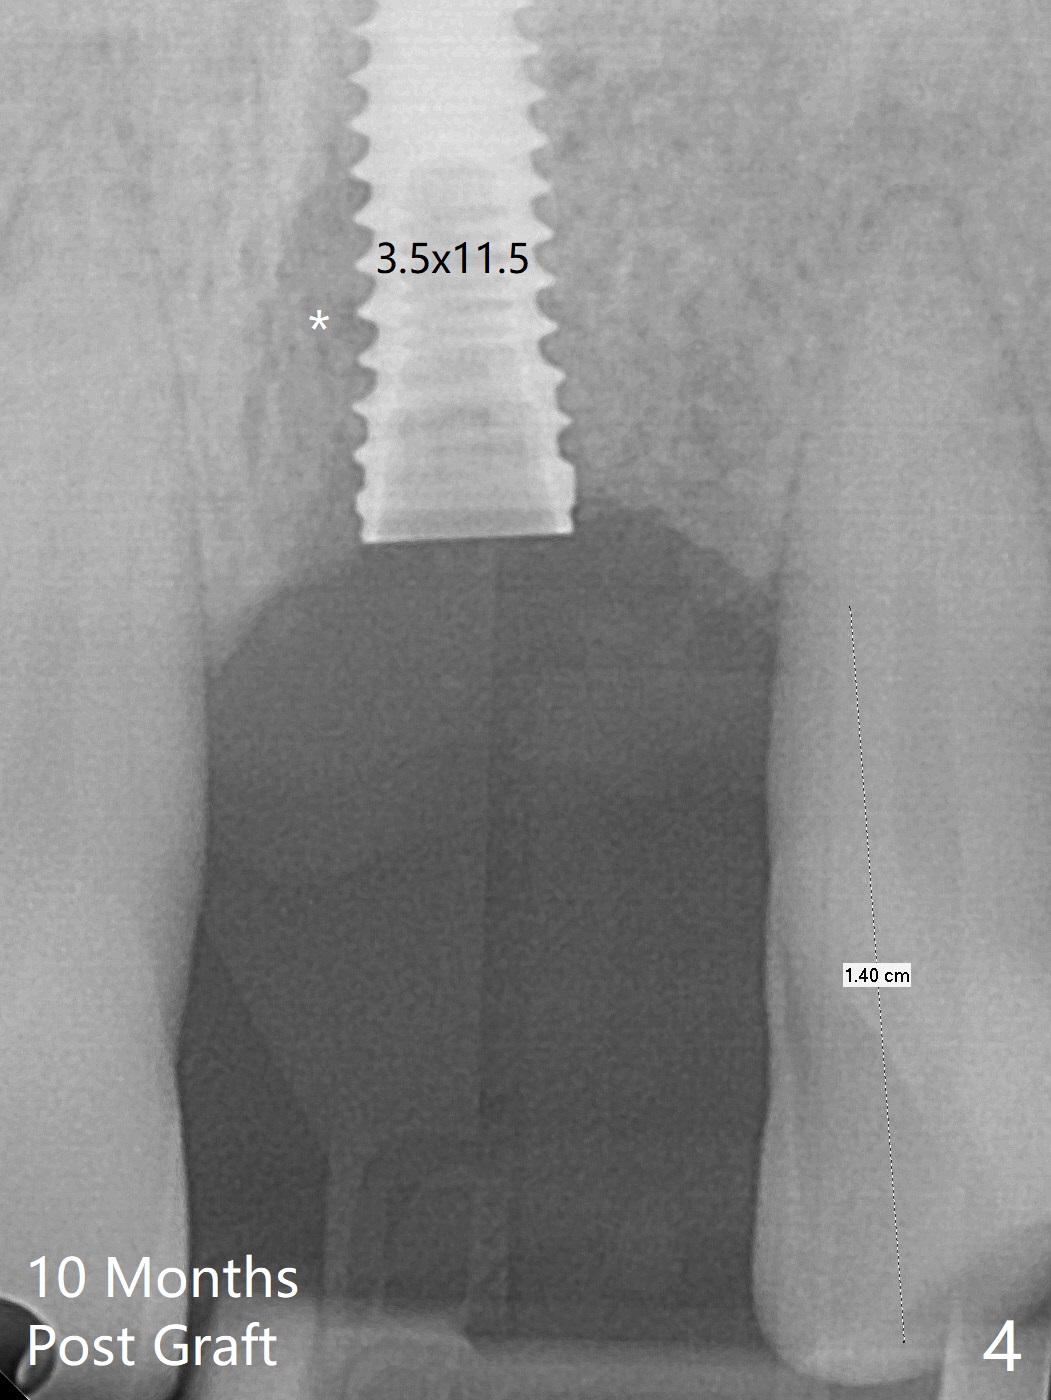

左上1(图一)拔除,植骨,使用带钛架不可吸收膜(图二)后十个月准备植牙(图三),在没有术中根尖片指导下(导板习惯),在牙槽嵴正中开始钻洞,第一个钻头最后一两个毫米觉得有突破感,但是颊侧舌侧没有穿孔,然后植入3.5x11.5毫米植体(图五,扭力>35 Ncm),术后射线表明植体接近切牙管(图四:*)。考虑到病人要离城,颊侧第一螺纹暴露(图六),舌侧骨板薄(图五),植骨,放置愈合基台(图七)。 术后十一天CT显示植体没有侵犯切牙管(图八:I);植体颊侧骨粉(箭头)似乎可以解释颊侧饱满(图九)。第二原因是减张缝合,胶原膜暴露(*),而下面骨粉没有暴露,以后伤口应该是二期愈合。